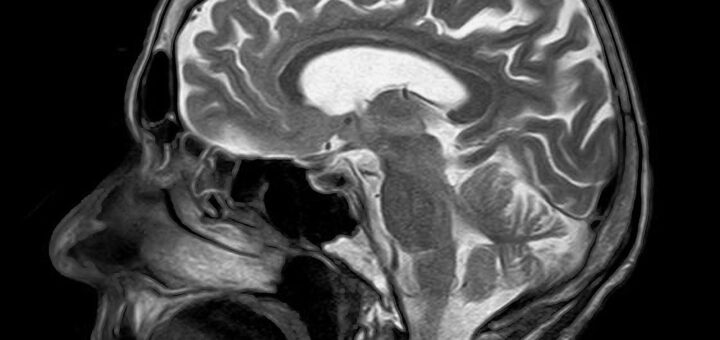

When Tiny Molecular Changes Reshape the Entire Brain

What fascinates me most about neuroscience is how small molecular events can ripple out to affect the entire brain. A recent article in Nature Computational Science caught my attention because it attempts to do...